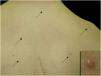

A 14-year-old boy with Down syndrome and a previous history of anorectal anomaly visited our Dermatology Department, complaining of asymptomatic eruption on his back. He had no family history of connective tissue nevi. Physical examination showed several red-brown or whitish papules on his back (Fig. 1). There were no eruptions in other locations. One of the papules was removed under local anesthesia. A biopsy specimen revealed relatively well-circumscribed areas with increased collagenous fibers in the upper to mid-dermis (Fig. 2A). Lack of elastic fibers as compared with surrounding dermis was observed in Elastica Masson (Fig. 2B), Elastica van Gieson and Weigert staining. A diagnosis of collagenoma was made. No specific treatment was given.